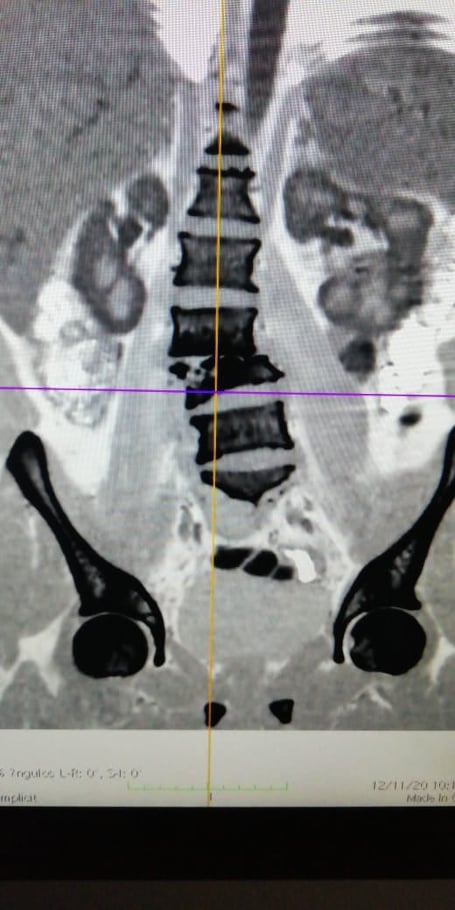

Al día siguiente, ecografía renal (Fig.2) reveló riñones levemente agrandados (riñón derecho de 12,7 cm de longitud y riñón izquierdo 13,5 cm; rango de referencia, 10.1 a 12.8) 1 con ecotextura parenquimatosa normal. El riñón izquierdo tenía múltiples quistes y no había hidronefrosis. La TC de tórax, abdomen y pelvis, realizado sin contraste intravenoso, reveló esplenomegalia pero sin otra cosa destacable.

Figura 2. Imágenes ecográficas renales.

En las imágenes ecográficas longitudinales de los riñones derecho e izquierdo (paneles A y B, respectivamente), se conserva la ecotextura renal. Quistes renales (Panel B, flechas) están presentes en el riñón izquierdo.